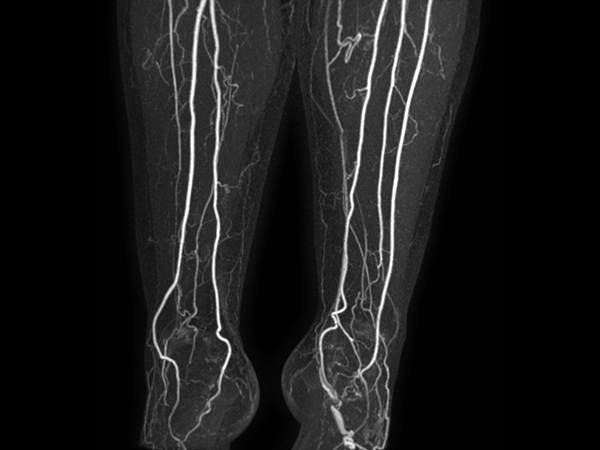

mDIXON MRA (MIP) - Lower leg